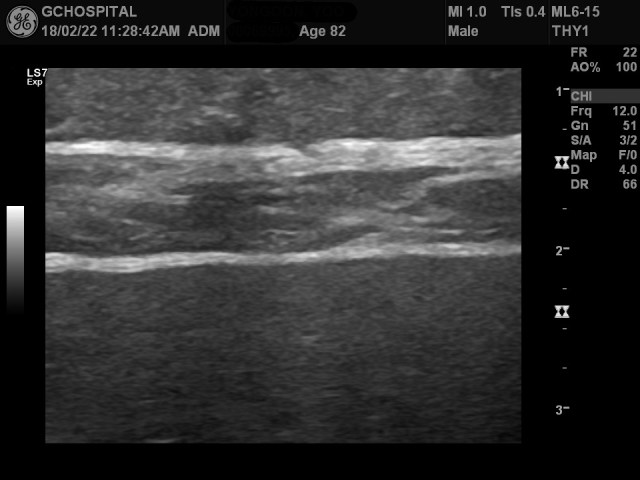

다른 부위에서 얻은 영상에서는 간 피막의 윤곽이 더 뚜렷하게 울퉁불퉁해보입니다.